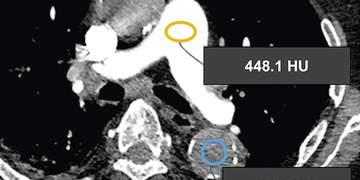

Die beiden nachfolgenden Monitoringbilder veranschaulichen deutlich den Unterschied der Kontrastierung beim Einsatz des Contrast Boosters.